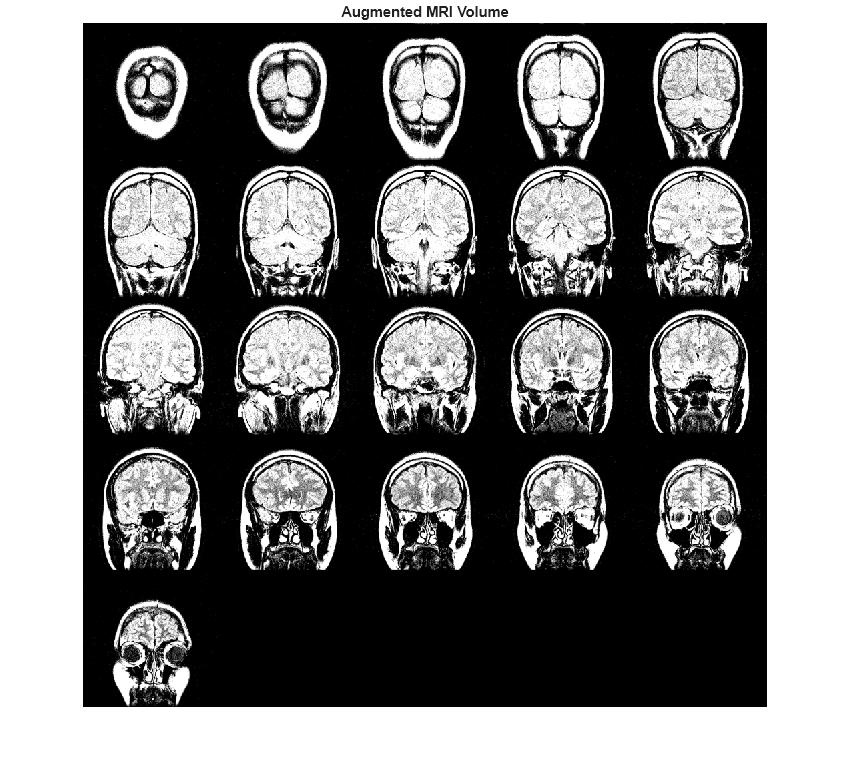

You can use data augmentation to increase the variety and quantity of training

data in deep learning applications, especially when available training data is limited, as is

typical in medical imaging. Data augmentation can be intensity augmentation, geometric

augmentation, or color augmentation. The jitterIntensity function performs

intensity augmentation of grayscale images and intensity volumes by randomly augmenting their

brightness, contrast, and gamma correction.

jitters the intensity of grayscale image or intensity volume J = jitterIntensity(I,Name=Value)I by

randomly selecting brightness (shifting of intensity), contrast (scaling of intensity), and

gamma correction values. To specify ranges for these values, use the corresponding